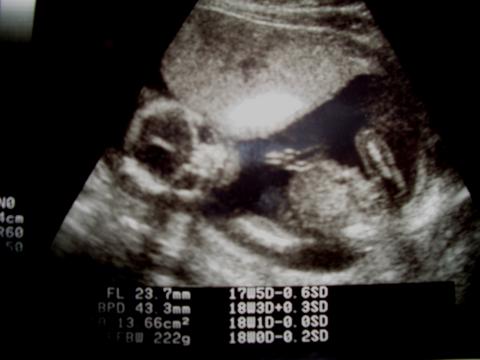

エコーといってお腹の中を見ることができる機械があるのですが、

骨格などがみえるので、どういう体勢でいるか、どっちを向いているかなどを確認できます。

プリントしてもらったエコーの写真には、

赤ちゃんが[:チョキ:]ピースしているように見えるものがありましたっ[:ぎょ:][:星:]

っで、性別は『8割男の子ですね。ここに見えている男の子の印が、

へその緒と間違って見える場合もありますが・・・次回も、確認しましょう。』と先生に言われました[:あひ:]